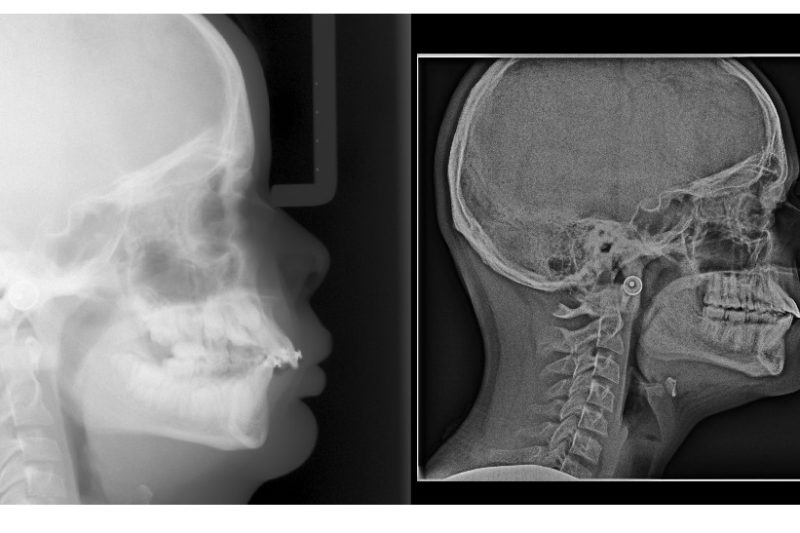

Been doing this for 19y, but I’m still amazed how my work can change a person’s look/life in just a year!